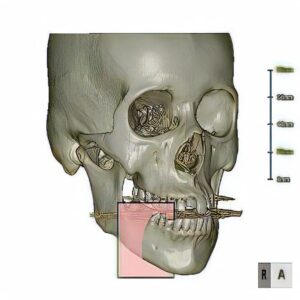

当院では、ステントを作成後、あご骨まわりのCT撮影を行い、事前に骨の状態や骨の中の血管・神経などの位置、インプラントを入れる位置を確認しています。

ステントとは、マウスピースのような形状をしており、インプラントを植え込む際の補助具です。

人工の歯を入れるわけですから、かみ合わせはもちろんのこと、周囲の歯に合わせて大きさや傾きなど、歯の設計をする必要があります。その補助となるのがステントです。上下の歯形をとり、これに合わせてステントと呼ばれるマウスピースを作成します。

このステントを装着した状態で、CT撮影を行い、どこにインプラントを入れ、どのように歯を並べられるかを調べます。同時に、撮影データを使いパソコン上で手術シミュレーションを行うことにより、手術前に上記の偶発症・合併症などの手術リスクを評価していきます。

また、シミュレーションを行った角度を寸分違わず行うために、ガイドと呼ばれるマウスピースを作成します。

ステントは「歯を設計するためのもの」で、ガイドは「手術をするためのもの」と考えて頂ければ良いでしょう。